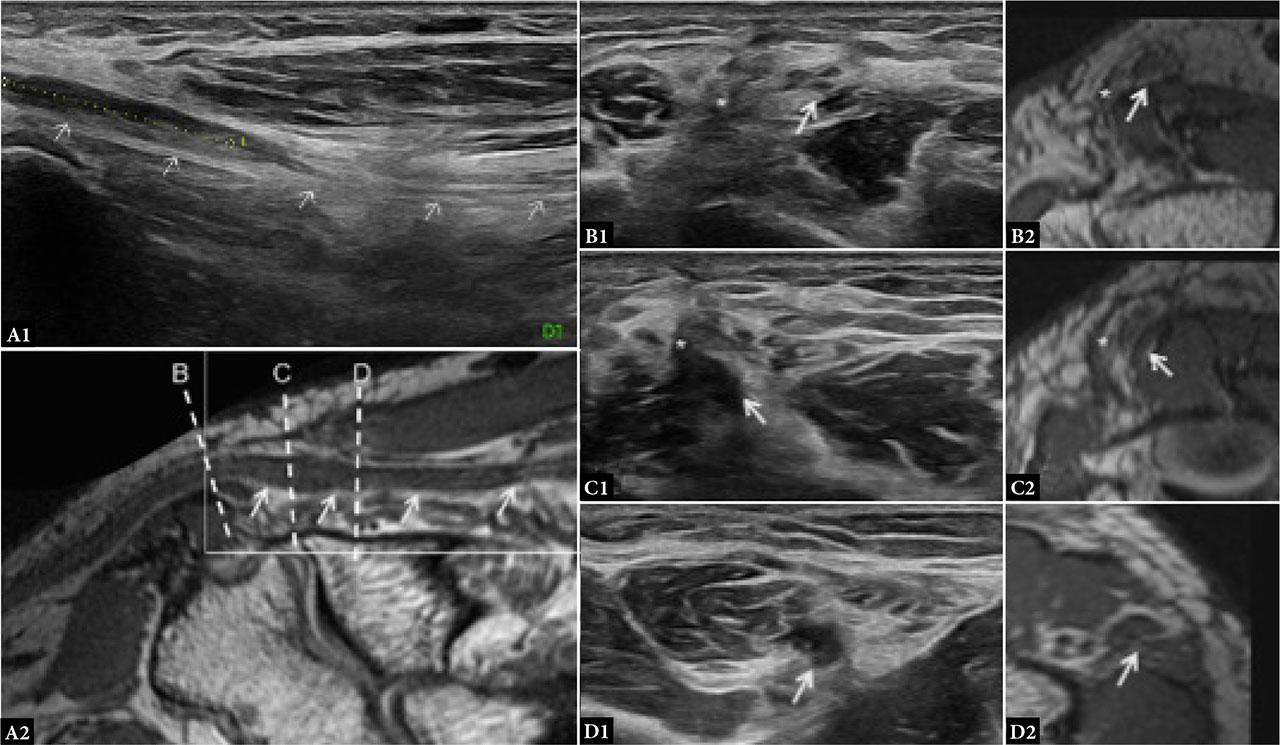

Both MRI and US often reveal persistent postoperative edema along the nerve. Linear signal changes and disruption of perineural fat planes are expected, whereas retraction or ring-like fibrosis should raise concern for re-entrapment. Kinking or tethering at entry or exit points – commonly the arcade of Struthers proximally or distal FCU fibers – can compromise outcomes. Secondary entrapment at the level of the arcade of Struthers (Fig. 5) has been reported more commonly following anterior transposition, likely due to tethering of the nerve from its altered course(4,28). Additional complications include neuroma formation, perineural scarring, hematoma, and seroma.

Ultrasound is the modality of choice for assessing dynamic nerve mobility and identifying instability. Postoperative scarring (Fig. 6) typically appears as hypoechogenic, noncompressible tissue enveloping the nerve. MRI, by contrast, is optimal for visualizing deep muscular compartments and evaluating for nerve oedema, muscle denervation, and the integrity of surgical corridors. T2-weighted hyperintensity and loss of fascicular detail are consistent with oedema or neuritis, while chronic denervation manifests as fatty infiltration of the affected muscles. Post-contrast sequences can differentiate active inflammation, neuroma, or granulation tissue. Postoperative fibrosis appears as a thick rind-like enhancement on T1-weighted images and hypointense tissue on T2-weighted images.

Ulnar nerve impingement at the level of postoperative scar following ulnar transposition: A–D1. Ultrasound; A–D2. PD SPACE reformat. In A2, the square corresponds to the US view in A1 and dotted lines correspond to the axial images in B–D. Arrows: ulnar nerve. A. Longitudinal view showing focal hypoechoic ulnar nerve with caliber change. This alteration is clearer on US than MRI. B. Ulnar nerve proximal to the scar (*); the fascicular pattern is preserved. C–D. At the scar level (* in C), and slightly distally (D), the ulnar nerve appears distorted and hypoechoic, with loss of normal fascicular architecture